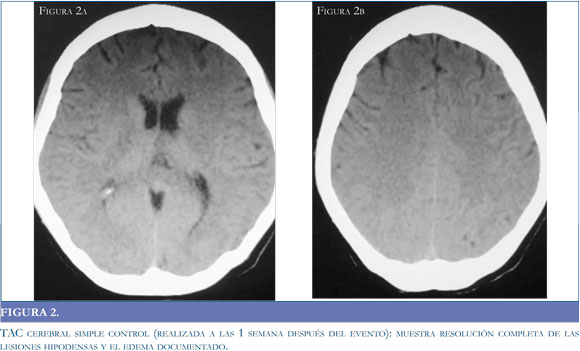

La tomografía puede no ser el método de elección en consideración a sus características operativas, pero es un recurso de fácil acceso para la aproximación diagnóstica. Si bien la tomografía puede ser negativa en la etapas tempranas del síndrome (39), está documenta la presencia de lesiones hipodensas habitualmente simétricas1 en la sustancia blanca de los territorios posteriores y gangliobasales (34) (Figuras 1 a y b); con el desenlace clínico de la patología, las imágenes tomográficas muestran una resolución de las hipodensidades descritas en el momento de mayor intensidad clínica (Figuras 2 a y b).